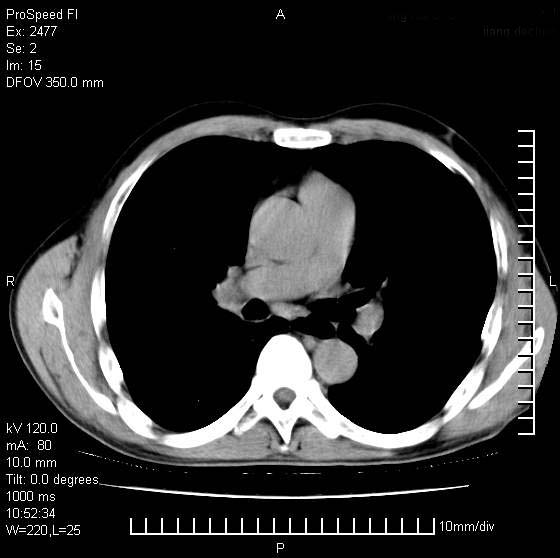

以下是引用天南地北在2007-10-9 14:29:00的发言:[br]1:右上肺结核[br]2:右肺下叶肿块:不支持肺癌,首先考虑炎性病变-肺脓疡可能性大[br]理由:1:临床病史支持,肺脓肿症状不明显应该是不规则服药造成。[br] 2:肿块边缘模糊,周围可见炎性渗出,长毛刺,内见支气管征,不过有点不规则。[br] 我感觉下肺癌这个诊断有点偏左,建议积极抗炎治疗后复查

以下是引用卜一在2007-10-9 15:55:00的发言:[br][br] [br] 1:右上肺结核[br]2:右肺下叶肿块:不支持肺癌,首先考虑炎性病变-肺脓疡可能性大[br]理由:1:临床病史支持,肺脓肿症状不明显应该是不规则服药造成。[br] 2:肿块边缘模糊,周围可见炎性渗出,长毛刺,内见空气支气管征,不过有点不规则。[br] 我感觉下肺癌这个诊断有点偏左,建议积极抗炎治疗后复查![br]支持! [br] [br] [br]

以下是引用wxy7406在2007-10-9 21:02:00的发言:[br]结合临床病史首先考虑感染性病变,但周围型肺癌不能除外,1.患者年龄偏大2.临床有咯血3.(也觉得是最重要的一点)病灶内有偏心性空洞。

以下是引用王仕学在2007-10-9 13:48:00的发言:[br]右下肺周围性肺癌可能性大,最好活检吧

以下是引用hhcckk在2007-10-9 15:18:00的发言:[br]右上肺病灶考虑结核,病灶多种形态并存(纤维化、增殖性病灶并存)[br]右下肺病灶比较难说,个人意见更趋向于“天南地北”的诊断----肺脓肿[br]1、病人有明显的寒战,高热,肿瘤病人很少出现[br]2、病灶周围的肺纹理走向柔和,没有肿瘤病灶常见的集束征[br]3、病灶边缘的毛刺较长,恶性肿瘤多为短毛刺[br]痰中血丝和病人的年龄是两个不利于良性肿块的因素,建议早点活检

以下是引用ydx_74在2007-10-9 15:53:00的发言:[br]右上肺结核,右下中心性肺癌可能大,肺门淋巴结肿大。